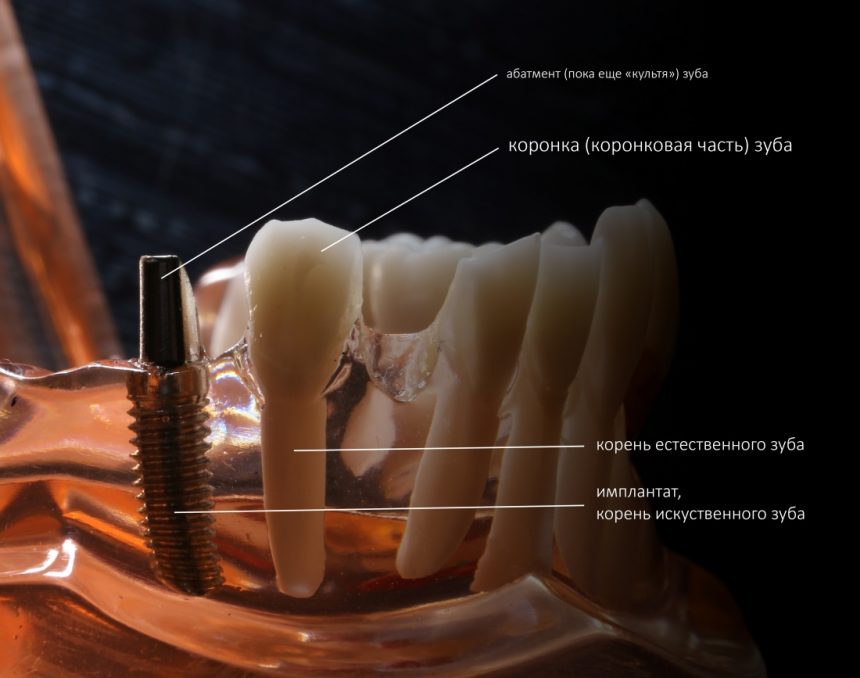

Как вообще устроен зуб? У него есть две части, коронка и корень:

Коронка зуба принимает на себя всё механическое воздействие при жевании, разговоре или просто при попытке кого-то укусить, в то время как корень передает и распределяет эту механическую нагрузку на челюстную кость. Для того, чтобы зуб нормально работал, не разрушался и не разрушал кость вокруг себя, его коронка должна находится в определенных пространственных отношениях как с соседними зубами, так и с зубами-антагонистами. Совокупно и применительно ко всему зубному ряду, это пространственное отношение называется прикусом: